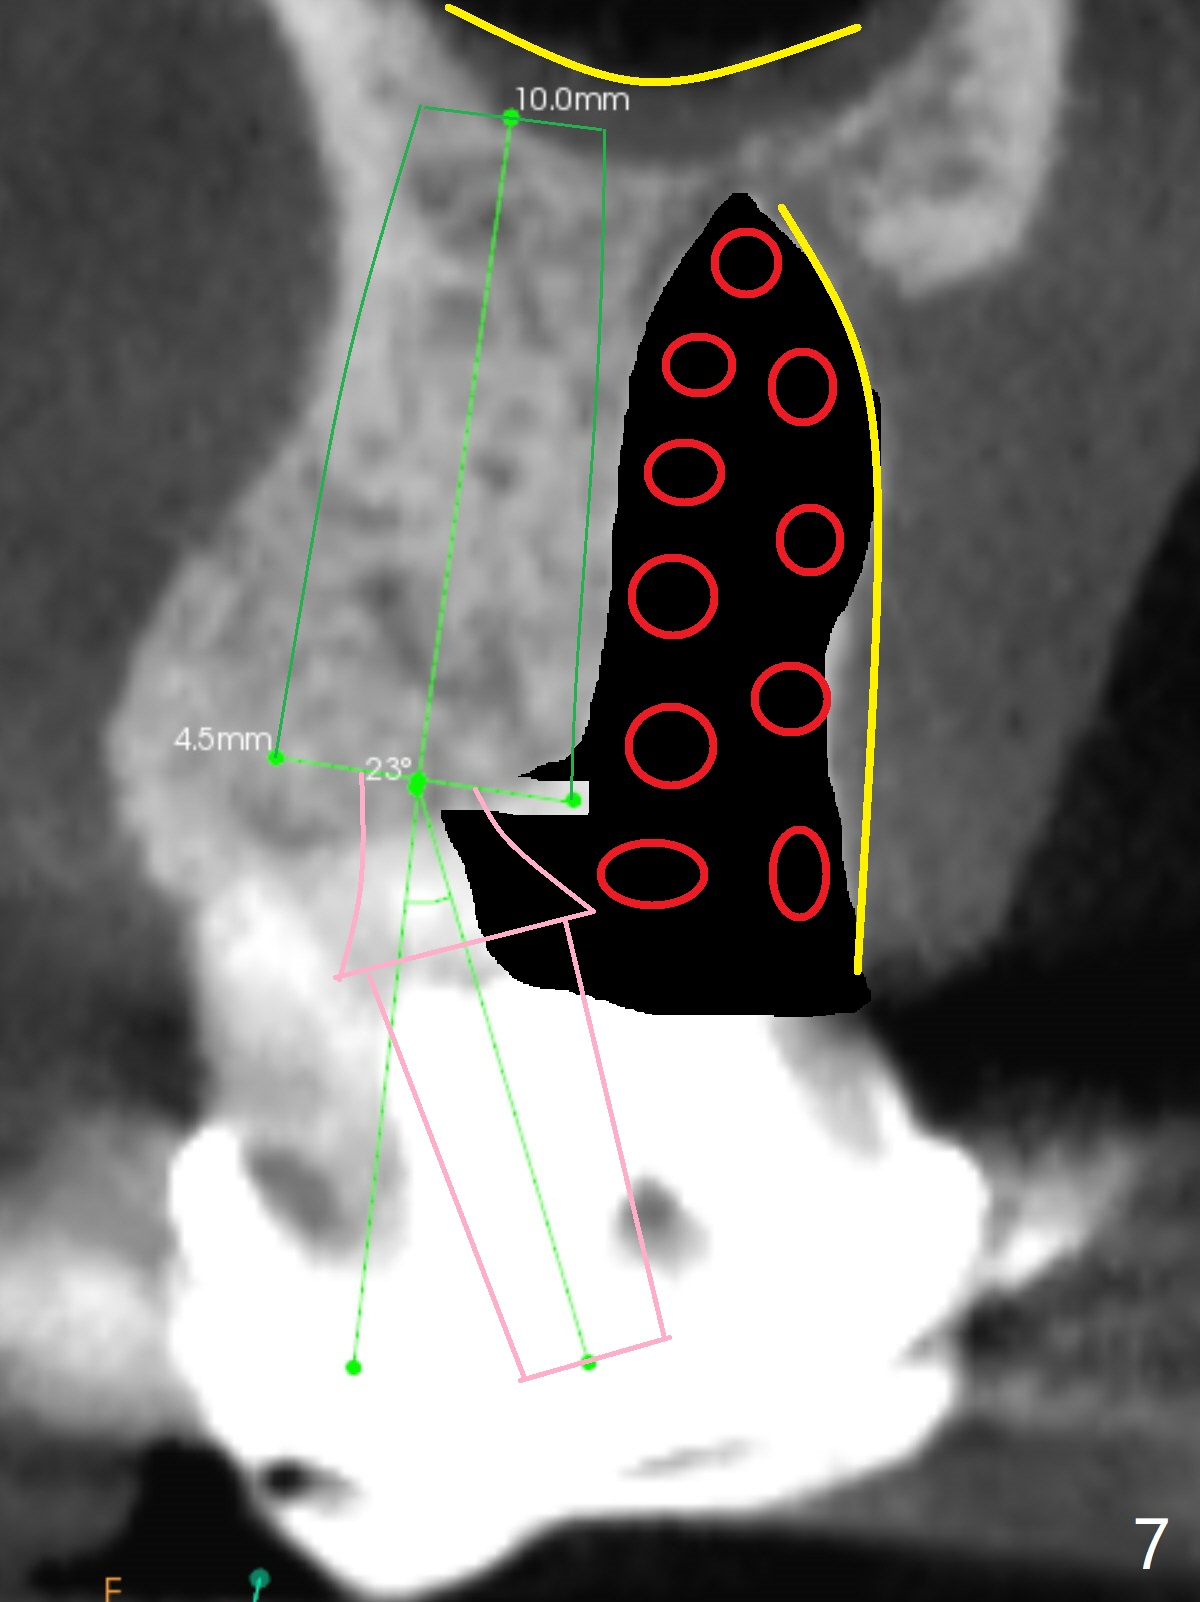

A 52-year-old woman has had chronic abscess associated with the tooth #3. The palatal root is exposed (Fig.1 P), suggesting root fracture. The apex of the mesiobuccal root seems to stick out of the buccal plate (Fig.2 *). The root canal filling is incomplete in the distobuccal root (Fig.3 *). The tooth appears to have guarded prognosis. Extraction and immediate implant is apparently a better option (Fig.4,5). It would be safer to start osteotomy in the middle of the remaining septum (Fig.6, as compared to Fig.5). After sinus lift with PRF membrane (Fig.7 yellow curved line) and implant placement (green), another piece of PRF membrane will be placed against the palatal wall of the socket, followed by bone graft (red circles) and a 25-degree angled abutment (pink).